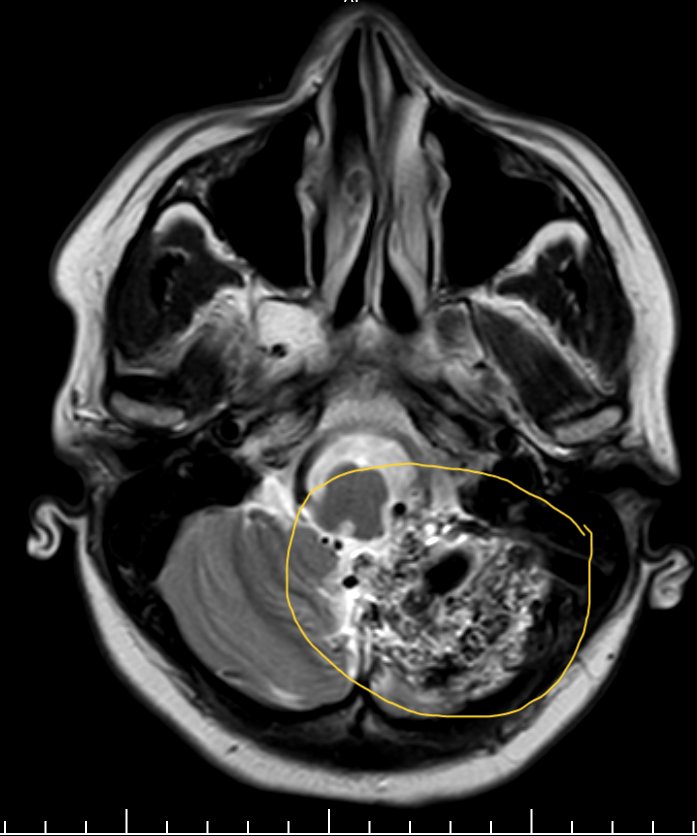

A 32yr♂️ presents to the ED with severe headache,blurred vision,confusion & 2 episodes of generalized tonic-clonic seizures.BP 190/110mmhg & MRI scan done👇.Diagnosis?management? #MedTwitter #MedX #NeuroTwitter #CardioTwitter #FOAMed @albertoortegana @IhabFathiSulima @elidyynwa

PeterItebimien's tweet image. A 32yr♂️  presents to the ED with severe headache,blurred vision,confusion & 2 episodes of generalized tonic-clonic seizures.BP 190/110mmhg & MRI scan done👇.Diagnosis?management?

(For doctors) Describe the findings and possible diagnosis? #neuroradiology #neurology #neurotwitter

hyderabaddoctor's tweet image. (For doctors)

Describe the findings and possible diagnosis?